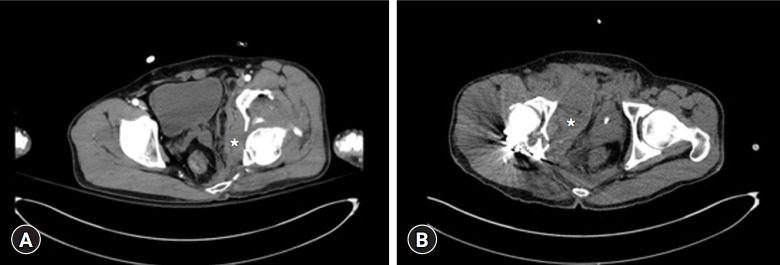

骨盆骨折是由高能创伤引起的,当伴有失血性休克时,死亡率增加到40%。骨盆骨折在解剖学上分为骨盆环断裂和髋臼骨折,每种骨折需要不同的治疗方法和入路。髋臼骨折也可由高能损伤引起,并可伴有失血性休克。盆腔骨折合并失血性休克的治疗选择包括血管栓塞、腹膜前盆腔填充物(PPP)和紧急剖腹手术。对于血流动力学稳定的患者,可以尝试早期全面护理,对于髋臼骨折(后柱),Kocher-Langenbeck入路是治疗的选择。本病例报告描述了在Kocher-Langenbeck入路治疗髋臼骨折伴骨盆环损伤的术后腹膜后出血伴血流动力学不稳定的抢救手术中使用PPP。患者出院时无骨移位或手术部位感染等术后并发症。虽然PPP通常被用作盆腔骨折并失血性休克的初始治疗方式,但它在治疗术后腹膜后出血并失血性休克方面也可能有价值。

Pelvic fractures result from high-energy trauma, and when accompanied by hemorrhagic shock, the mortality rate increases to 40%. Pelvic fractures are anatomically categorized as pelvic ring disruptions and acetabular fractures, each requiring different treatment methods and approaches. Acetabular fractures, which also result from high-energy injuries, may be accompanied by hemorrhagic shock. Treatment options for pelvic fractures with hemorrhagic shock include angioembolization, preperitoneal pelvic packing (PPP), and emergency laparotomy. In hemodynamically stable patients, early total care may be attempted, and for acetabular fractures (posterior column), the Kocher-Langenbeck approach is the treatment of choice. This case report describes the use of PPP as a salvage operation for postoperative retroperitoneal bleeding with hemodynamic instability following a Kocher-Langenbeck approach for an acetabular fracture with pelvic ring injury. The patient was discharged without postoperative complications such as bone displacement or surgical site infection. While PPP is commonly employed as an initial treatment modality for pelvic fractures with hemorrhagic shock, it may also be valuable in managing postoperative retroperitoneal bleeding with hemorrhagic shock.